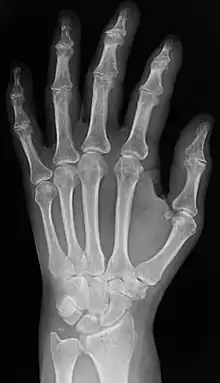

Radiography

Two forms of radiographic images are in use in medical imaging. Projection radiography and fluoroscopy, with the latter being useful for catheter guidance. These 2D techniques are still in wide use despite the advance of 3D tomography due to the low cost, high resolution, and depending on the application, lower radiation dosages with 2D technique. This imaging modality uses a wide beam of x rays for image acquisition and is the first imaging technique available in modern medicine.

- Projectional radiographs, more commonly known as x-rays, are often used to determine the type and extent of a fracture as well as for detecting pathological changes in the lungs. With the use of radio-opaque contrast media, such as barium, they can also be used to visualize the structure of the stomach and intestines – this can help diagnose ulcers or certain types of colon cancer.